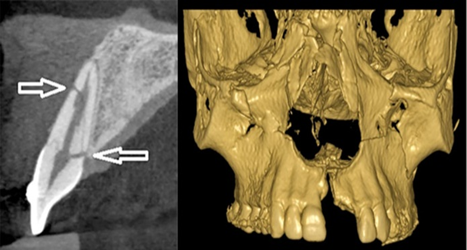

| - CBCT trong chẩn đoán răng khôn mọc lệch/ mọc ngầm: Nhờ có sự giúp đỡ của CBCT, bác sĩ có thể lường trước được mối liên quan của dây thần kinh với chân răng khôn cũng như quyết định thực hiện kỹ thuật nhổ răng khôn trong một lần duy nhất hay chỉ cắt thân răng khôn, chờ chân răng trồi lên. | | |

Hàng năm, có rất nhiều bệnh nhân đến thăm khám và được tư vấn chụp Cone Beam CT tại Bệnh viện đa khoa tỉnh Quảng Trị đem lại kết quả điều trị thành công cao. Dưới đây là một vài trường hợp bệnh nhân cụ thể điều trị tại Khoa Răng Hàm Mặt: - Trường hợp 1: Bệnh nhân nữ, 33 tuổi đến khám với lý do đau nhức vùng răng 38, 48 nhiều lần. Thăm khám trên lâm sàng, răng 38, 48 lệch gần, nhú 1 phần thân răng trên cung hàm, nướu tương ứng sưng đỏ. Bệnh nhân được chụp XQ răng toàn cảnh thường qui nghi ngờ có nguy cơ cao chèn ép ống thần kinh hàm dưới, gây nguy cơ chấn thương thần kinh cao khi phẫu thuật nhổ răng khôn. Bệnh nhân được chỉ định chụp Cone Beam CT kiểm tra, qua các lớp cắt đã thấy rõ hình ảnh răng khôn hàm dưới mọc lệch chèn ép thần kinh .